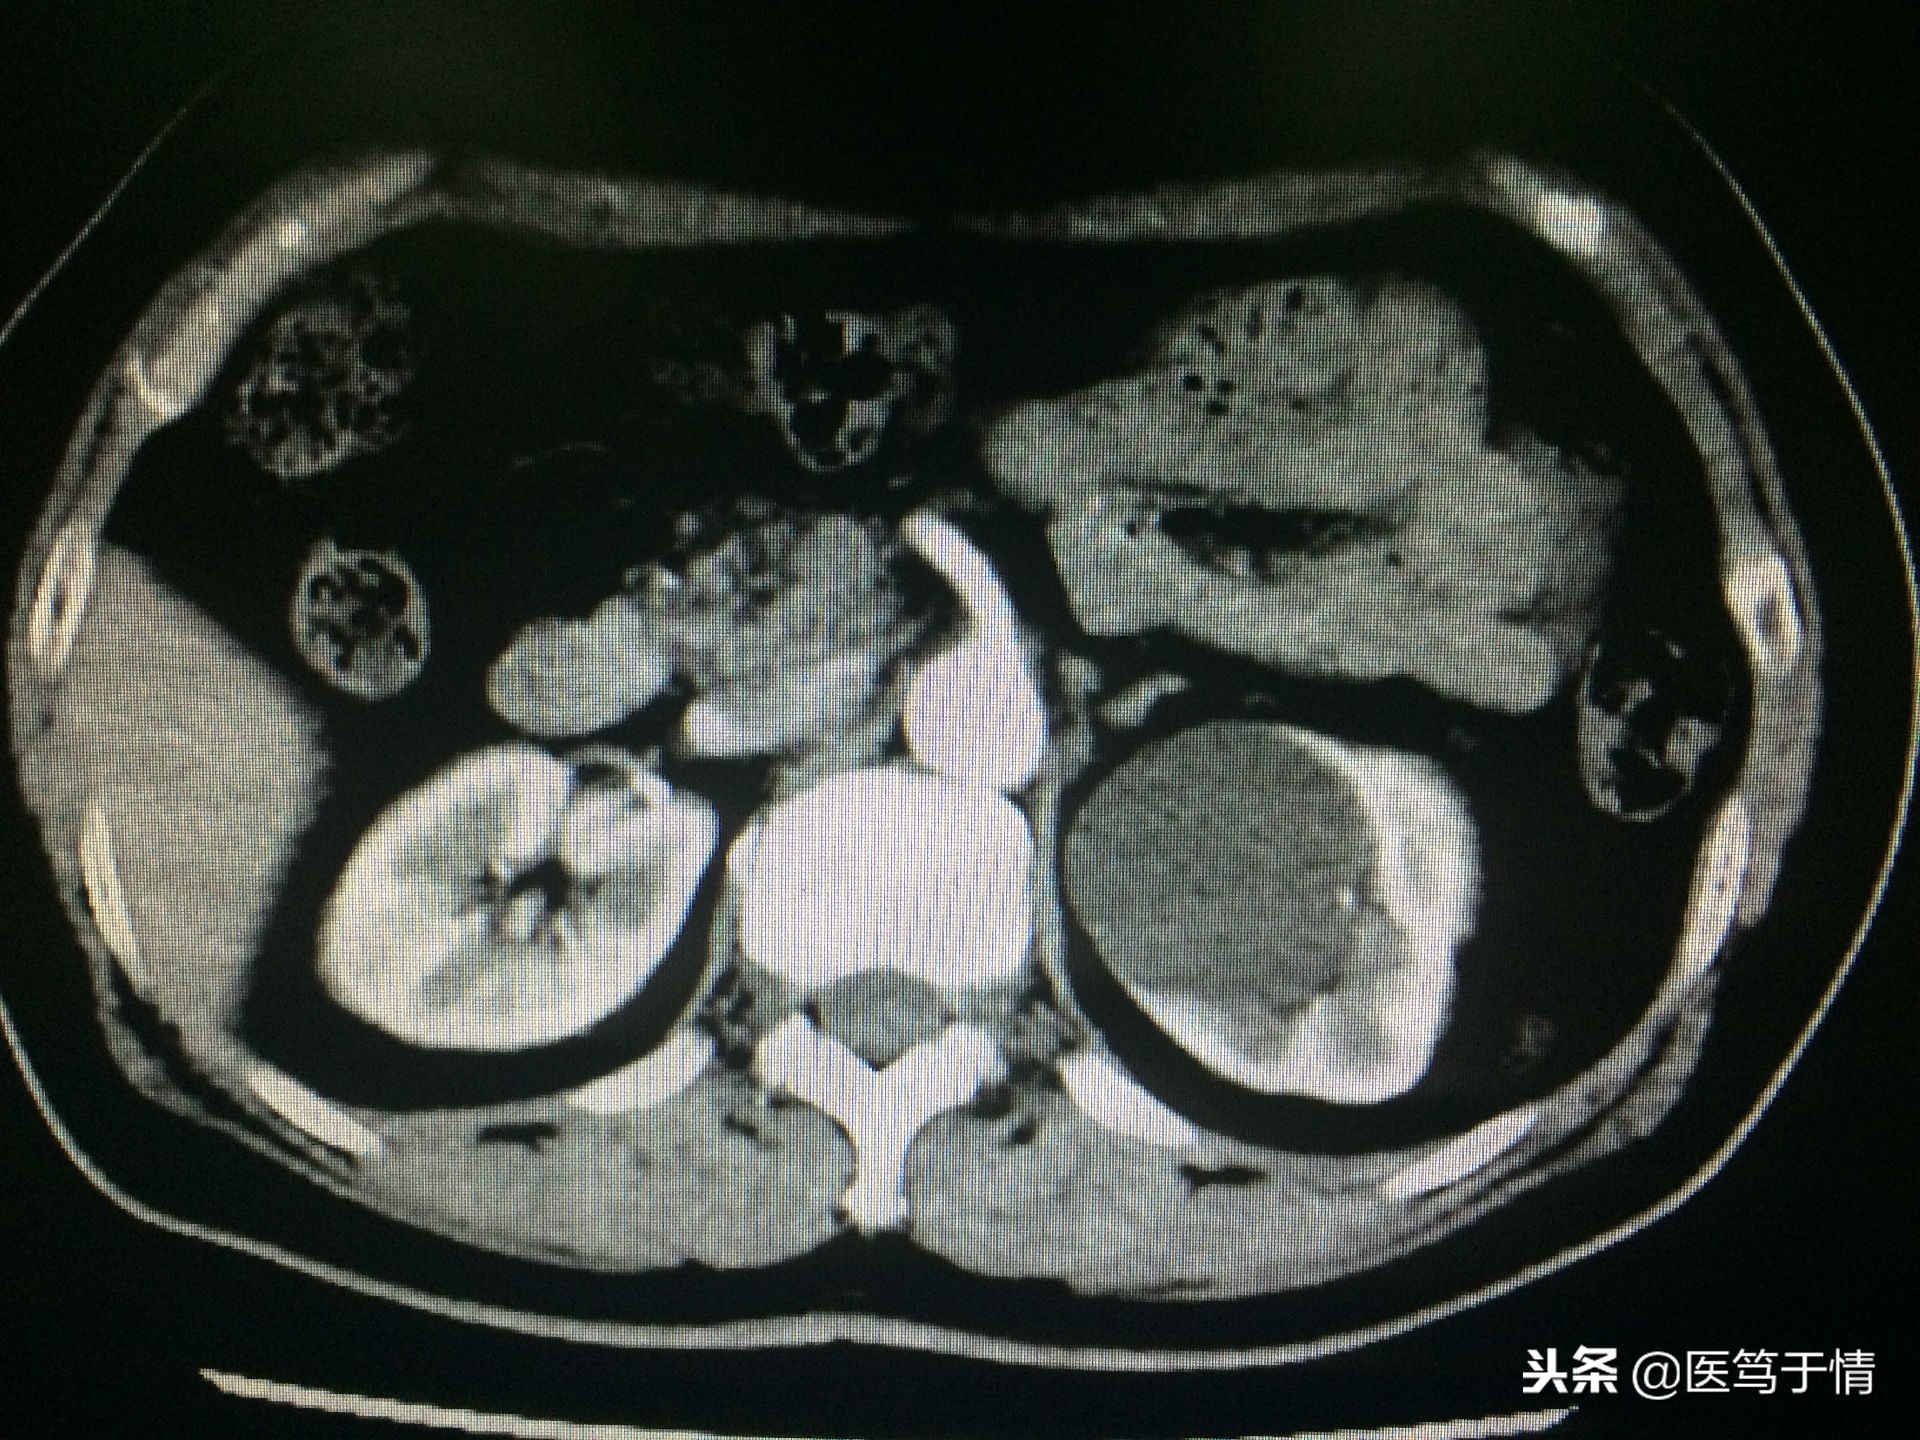

图二:女,60,左肾囊肿;2016年4月腹腔镜肾囊肿去顶;